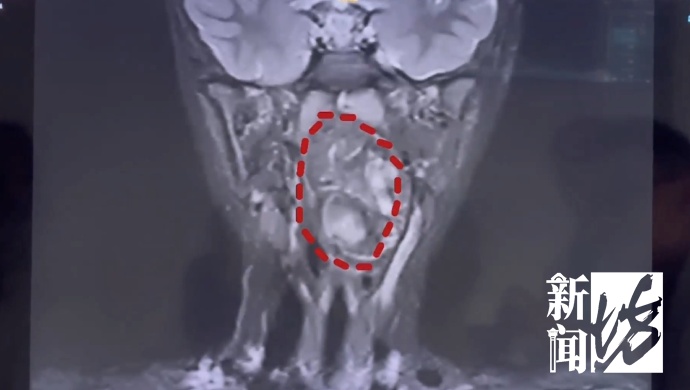

复旦大学附属儿科医院

耳鼻咽喉头颈外科副主任 陈超:

我们可以看出它有脂肪,有软骨,这是一对双胞胎,一个是我们正常的人发育成的人,另外一个他可能残留在这个咽旁间隙里面,就发育成了这样的一个畸胎瘤。

6岁男孩的口咽腔大概在8公分左右,这个孩子的肿瘤已经高达6公分多,整个气道已经完全被这个膨大的肿瘤占据了,只有一条黑颜色的线,这是它透气的空间,再让它继续膨胀下来,它首先出现的一个症状应该是呼吸道的梗阻窒息,会出现窒息致死的可能。